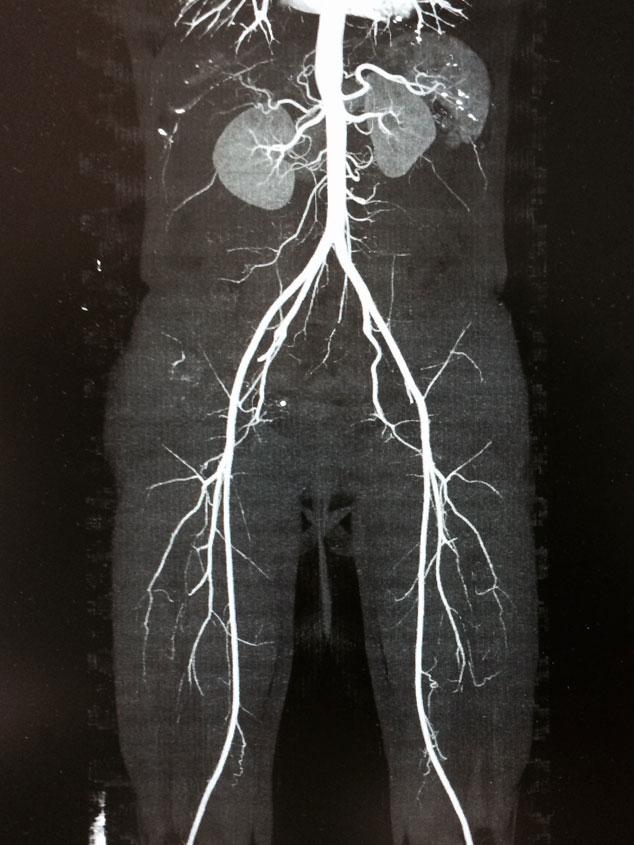

El sistema venoso de nuestras extremidades inferiores está equipado con válvulas que mantienen el flujo sanguíneo en dirección al corazón, conservando una presión baja de forma constante. Cuando las válvulas del sistema superficial pierden su función, las venas se distienden y estas permiten el regreso de la sangre, entorpeciendo su flujo (reflujo venoso). Esto aumenta la presión, especialmente al estar de pie o sentados por periodos prolongados.

Las venas comienzan a presentarse más gruesas y empiezan a volverse visibles bajo la piel. Después, toman trayectos curvos erráticos engrosándose cada vez más y saltándose a través de la piel. Con el riesgo de resultar muy dolorosas, esto ocasiona muchas molestias que perturben de manera importante la calidad de vida del paciente, pudiendo complicarse y produciendo úlceras venosas, sangrados y coágulos.

Las várices, son la consecuencia de la dilatación de las venas superficiales. Ya sea por disfunción o destrucción de sus válvulas (reflujo venoso), o bien por la obstrucción parcial o total en su flujo. Causando un aumento de presión en las mismas, siendo la causa más común por reflujo.